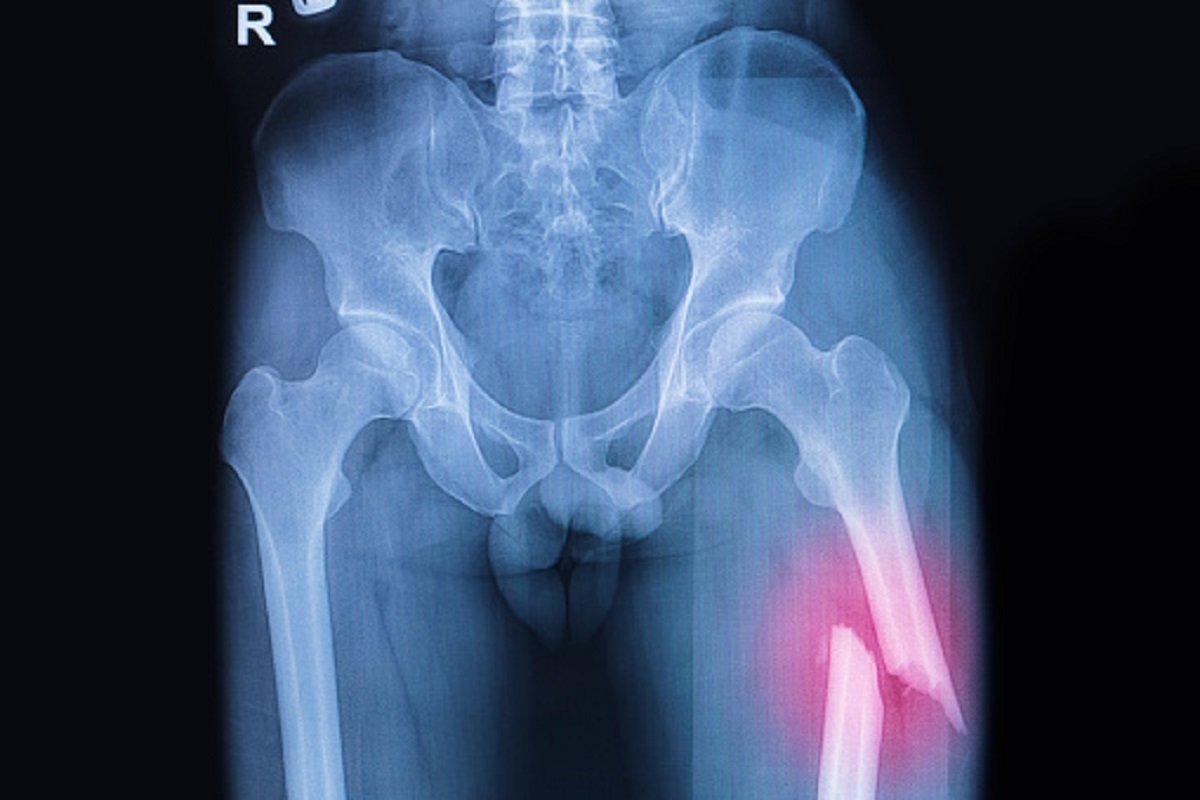

Rendgenski snimak je prikazao prelom butne kosti, ali njegova priča nije imala smisla ljekarima, prenosi “Oddity Central”.

Oni su odlučili da istraže slučaj i ispitaju pacijenta o njegovom opštem zdravlju, navikama, ishrani i načinu života. Uz to, urađena je analiza gustine kostiju koja je dala zabrinjavajuće rezultate.

Ispostavilo je da je slična gustini kostiju 80-godišnjeg muškarca!

Testovi su pokazali da ne pati od drugih bolesti, pa je zaključeno da je prelom posljedica krhkih kostiju, loše ishrane i manjka fizičke aktivnosti.